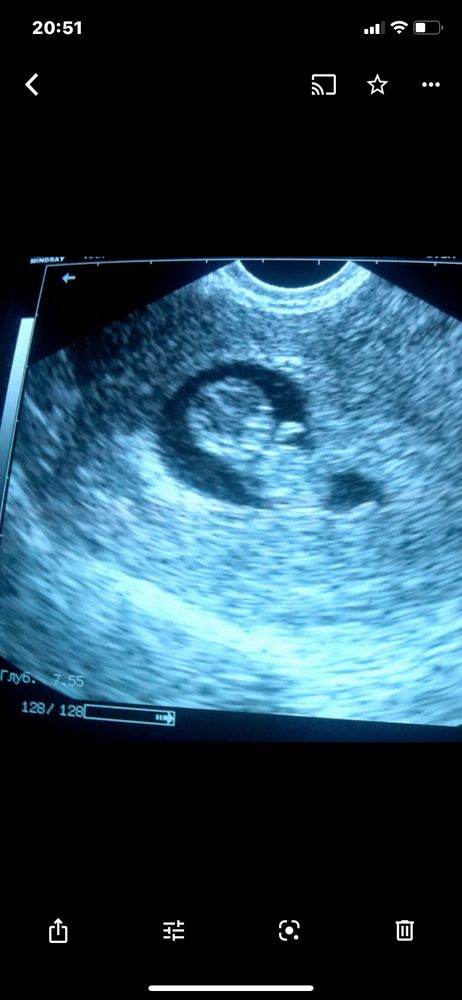

Честно сказать для меня это странно. Тест показывает слабую полоску. Сегодня 28 день цикла из 28. Ничего не болит. Вчера немного тянуло поясницу и яичник. Тошнит иногда, и слабость, спать хочется днем очень. Волнует грудь она обычная. Во время пмс всегда болит и набухает. Тут вообще тишина. Я прям в сметении. В первую беременность, грудь не помню б

Собственно месячные были один день, от силы может прокладка набралась. Сейчас тошнит ,как и тошнило особенно утром, грудь побаливает не критично. Температура тела такая же как и до месячных 36.8-37 . Что это сбой или нужно как то проверить причину. Только как ?! Раньше такого не было. Цикл 26-27 дней . Месячные обычно идут 5-6 дней в прошлый цик